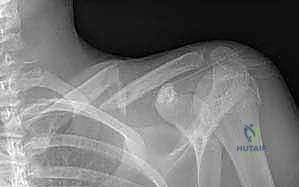

Clinical & Radiographic Imaging